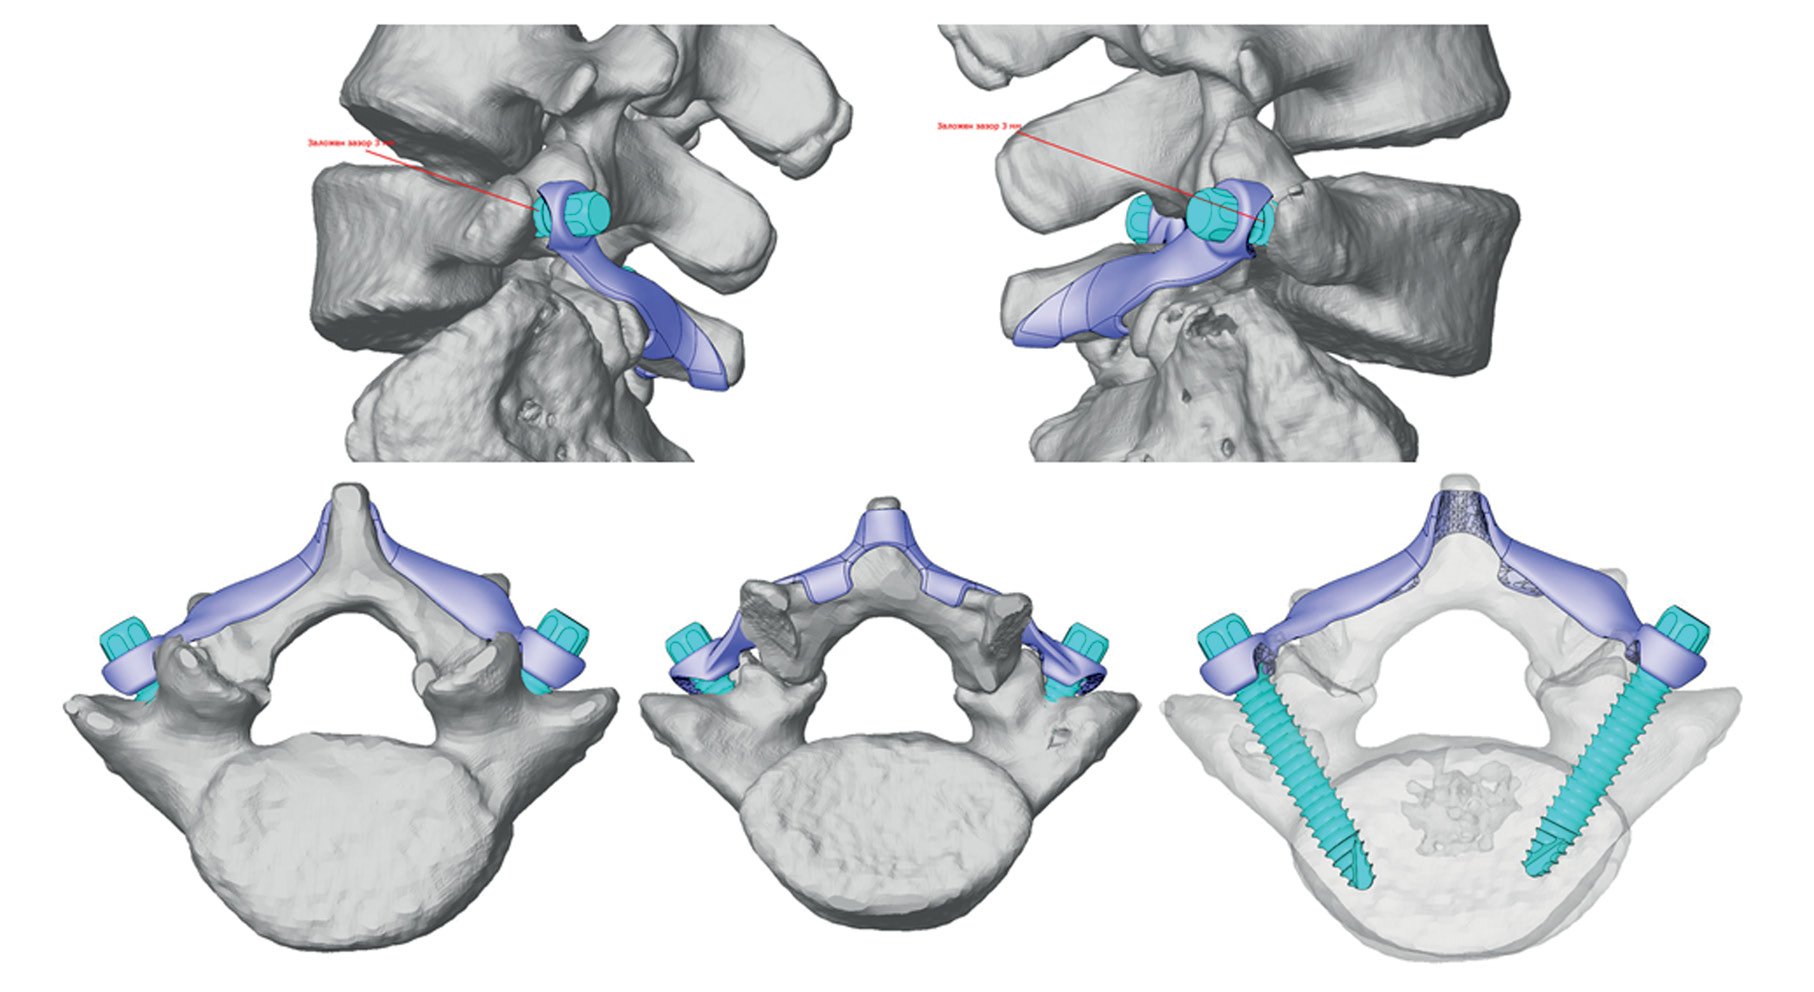

Рис. 2. Проект индивидуальной конструкции.

Fig. 2. The project of an individual implant.

Совместно с инженерами ООО «Конмет» выполнена компьютерная реконструкция сегмента L5-S1 на основании данных КТ. Изготовлена полноразмерная стереолитографическая модель сегмента L5-S1. На основании представленного проекта индивидуальной конструкции инженерами выполнено проектирование конструкции для восстановления целостности дужки L5 позвонка. Конструкция состояла из фигурной пластины, соответствующей анатомическому рельефу дорсальной поверхности дужки L5 позвонка и нижней поверхности остистого отростка L5 позвонка. Также на пластине спроектировано два крючкообразных выступа для суб-ламинарной фиксации, по наружным краям пластины с обеих сторон — отверстия в проекции точек ввода транспедикулярных винтов. Также спроектировано два транспедикулярных винта с головкой под торцевой ключ (рис. 2). Спроектированная конструкция изготовлена с использованием аддитивных технологий ООО «Конмет» из сплава Ti-6Al-4V ELI (рис. 3).